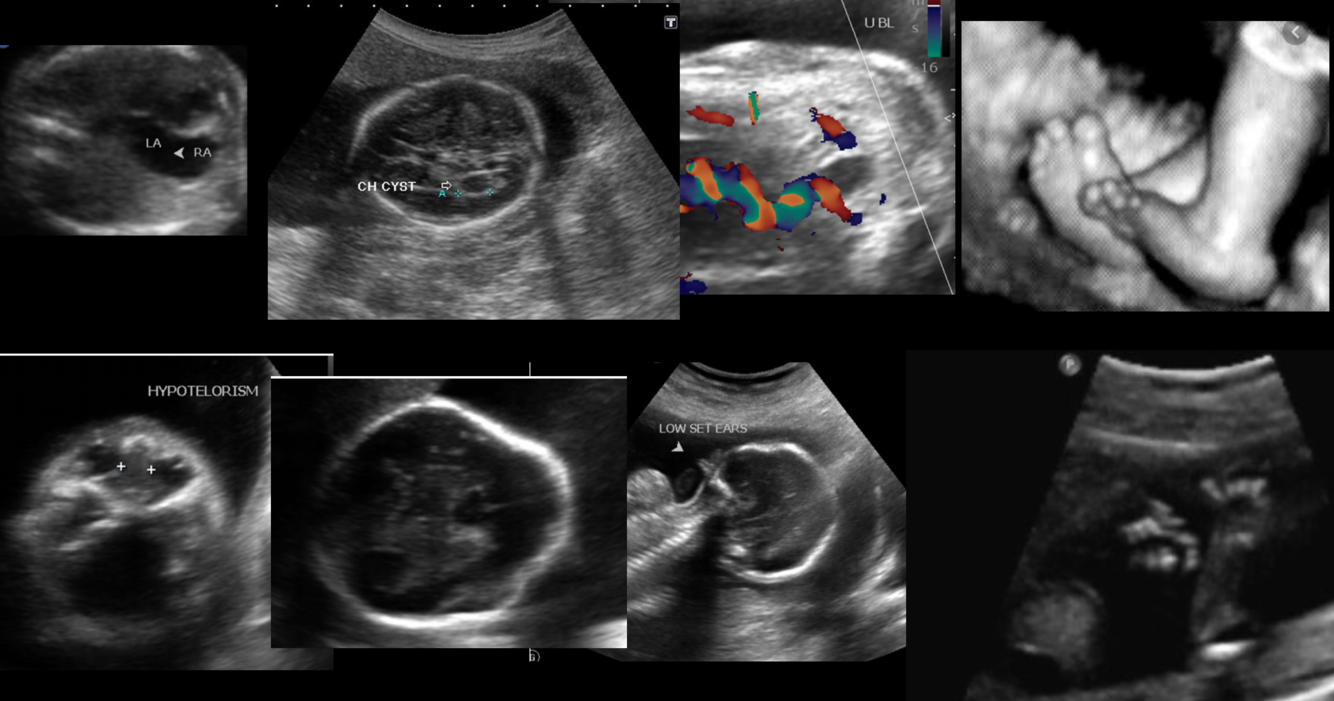

Antenatal ultrasound

Early 1st trimester ultrasound may show nuchal edema or a cystic hygroma similar to that of Turner syndrome. With subsequent scanning, some of the above individual clinical features may be present sonographically.

Trisomy 18 fetuses can have multiple anomalies in multiple systems. Over 130 features have been reported. Out of the three main trisomies, this trisomy has the highest incidence of major structural anomalies. Features include:

central nervous system or spinal abnormalities: 70%

choroid plexus cysts (especially if cysts are large and bilateral 6): found in 25-43% with trisomy 18

facial/calvarial abnormalities

micrognathia

dolichocephaly: strawberry skull: as a result of frontal lobe hypoplasia

low set ears

hypertelorism

skeletal abnormalities hand anomalies

clenched hands with an overlap of 2nd and 3rd digits: 80%

feet anomalies

rocker bottom feet: a typical feature